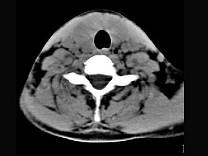

问题 40岁,女性患者,双侧甲状腺肿大,CT扫描如图所示,请选择最佳答案 ( )

选项 A、亚急性甲状腺炎 B、甲状腺瘤 C、甲状腺癌 D、甲状腺炎(桥本) E、弥漫性甲状腺肿

答案 D